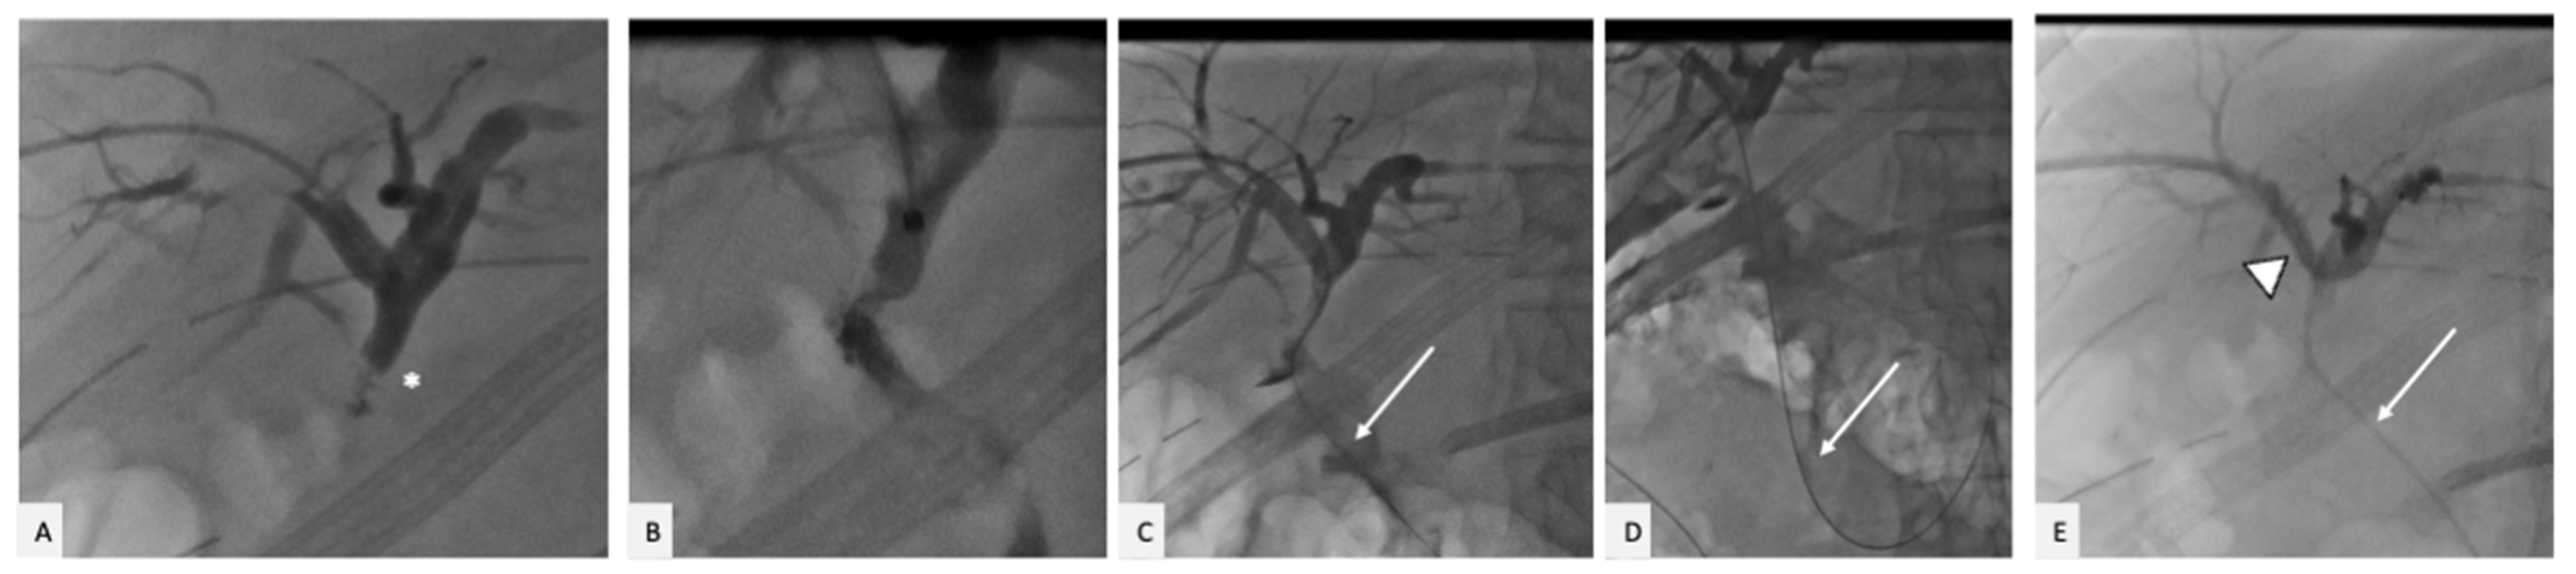

2. Case Presentation